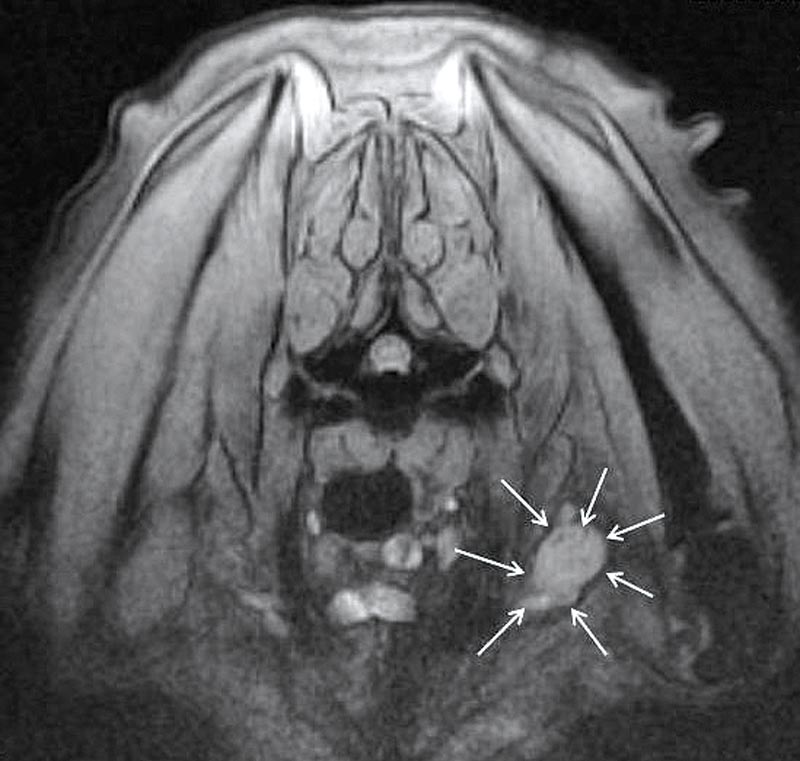

Paradoxical Vestibular Disease With Trigeminal Nerve Sheath Tumor In A Dog Semantic Scholar From semanticscholar.org

Paradoxical Vestibular Disease With Trigeminal Nerve Sheath Tumor In A Dog Semantic Scholar From semanticscholar.org

Thieme E-Books E-Journals. Magnetic resonance imaging MRI examinations from 18 dogs with a histologically confirmed peripheral nerve sheath tumor PNST of the brachial plexus were assessed retrospectively. The Siberian husky male 13 years old was brought to the Small animal clinic at Faculty of veterinary medicine in Belgrade with incapability of standing on the thoracic left limb. Peripheral nerve sheath tumors PNSTs in dogs develop from the. Diagnosis and Surgery - WSAVA2005 - VIN.

Magnetic resonance imaging MRI examinations from 18 dogs with a histologically confirmed peripheral nerve sheath tumor PNST of the brachial plexus were assessed retrospectively. The Siberian husky male 13 years old was brought to the Small animal clinic at Faculty of veterinary medicine in Belgrade with incapability of standing on the thoracic left limb. Malignant peripheral nerve sheath tumors. The presentation and associated pathologic changes in the. Peripheral nerve sheath tumor in a dog.

Source: semanticscholar.org

Source: semanticscholar.org